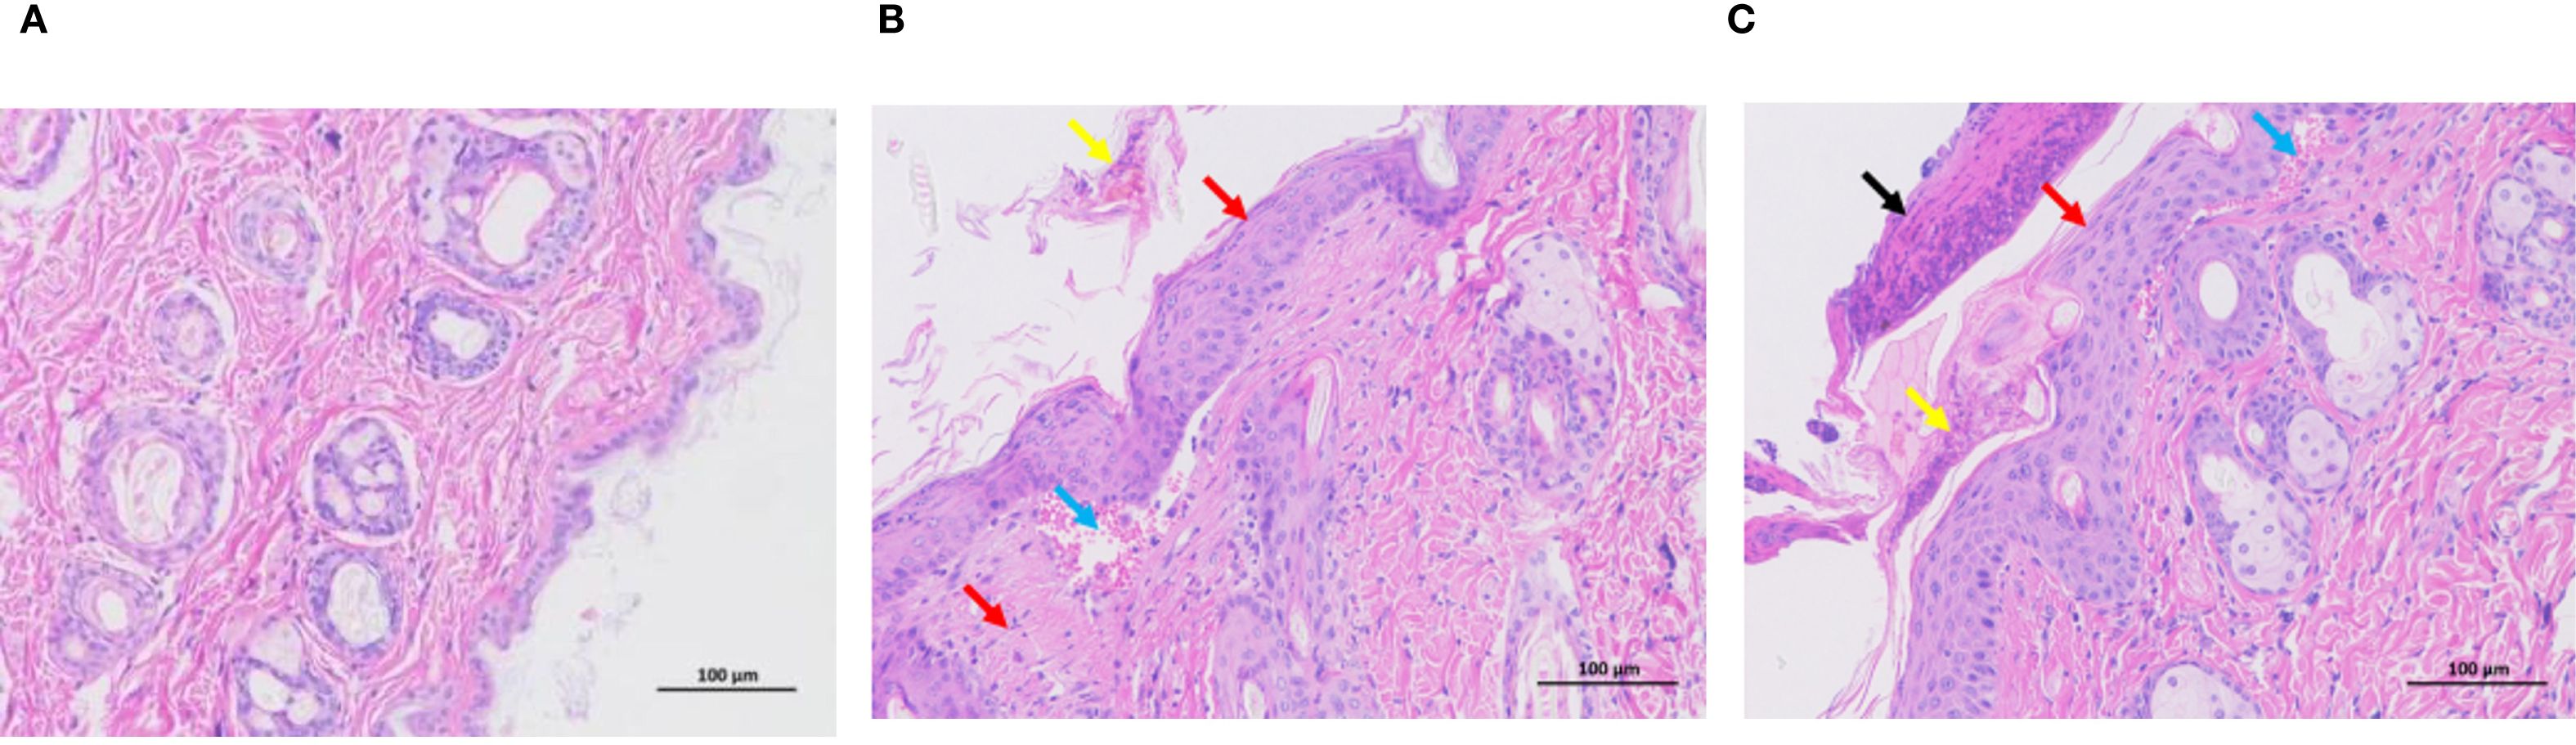

To characterize the dermatopathological changes induced by DNCB in the AD mouse model, we performed hematoxylin and eosin (H&E) staining on dorsal skin tissues. Control mice exhibited intact and normal epidermal and dermal structures without evident pathological abnormalities (Figure 1A). Compared to controls, the low-dose DNCB (0.1%) group displayed pronounced epidermal thickening (red arrows), focal parakeratosis (yellow arrows), mild hemorrhage (blue arrows), and moderate inflammatory infiltration (Figure 1B). Pathological changes in the high-dose DNCB (0.5%) group were markedly more severe, featuring substantial epidermal thickening (red arrows), hyperkeratosis (yellow arrows), conspicuous necrotic cellular debris (black arrows), and extensive inflammatory cell infiltration (blue arrows) (Figure 1C).

Figure 1. Representative histopathological changes of dorsal skin in mice (HE staining, ×200). (A) Control group: normal epidermal and dermal structure. (B) Low-dose DNCB group (0.1%): epidermal thickening (red arrow), incomplete keratinization (yellow arrow), mild hemorrhage (blue arrow), inflammatory cell infiltration. (C) High-dose DNCB group (0.5%): marked epidermal thickening (red arrow), hyperkeratosis (yellow arrow), necrotic cell debris (black arrow), more prominent inflammatory infiltration (blue arrow).